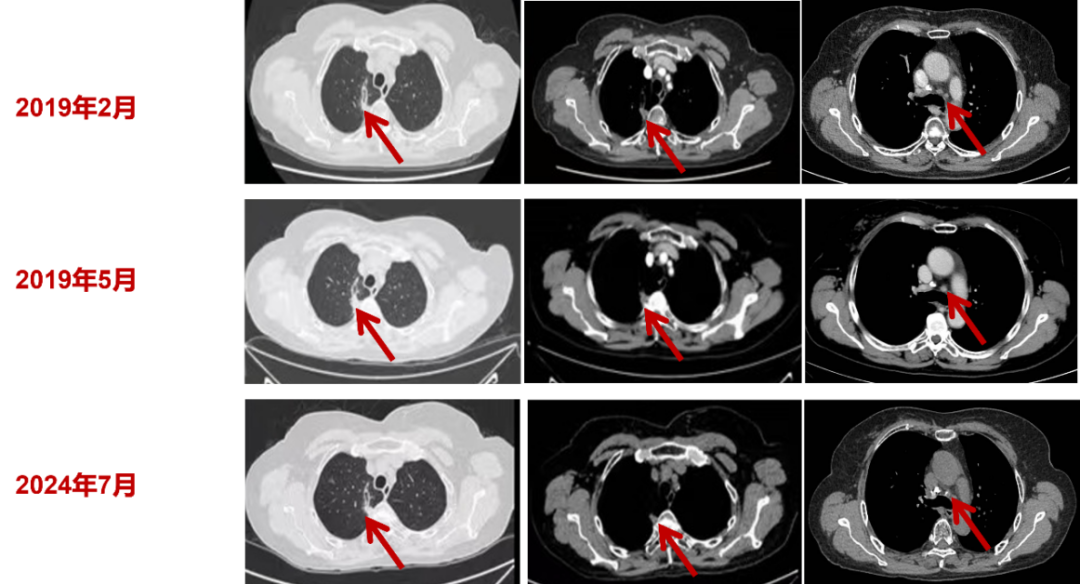

2. 截至2024年12月,患者依然在接受伊鲁阿克治疗,末次影像为2024年07月30日,未发生疾病进展。

3.疗效评估:达到最佳总缓解——病变稳定(SD),用药后第12周首次评价为SD,且一直持续至今。

图3 患者接受伊鲁阿克治疗期间影像学结果